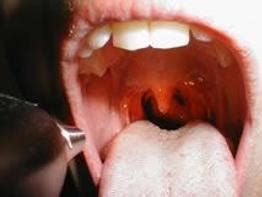

在冬季,儿科急诊室或五官科急诊常常可以见到一些夜间骤然声哑,频咳及呼吸困难的小婴儿。令家长们又惊又怕,那么如何对抗这个"凶猛"的喉炎呢?来听听上海新华医院周佳药师的讲解。